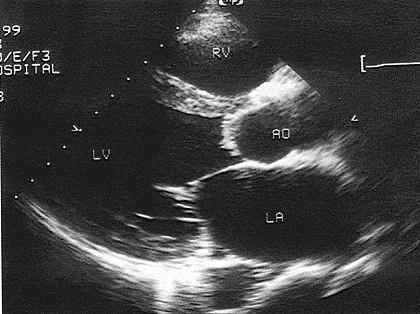

该病例最可能的诊断?(?)A.主动脉窦瘤B.主动脉瓣脱垂C.主动脉瓣下狭窄D.主动脉瓣畸形E.以上都不是

问题 该病例最可能的诊断?(?)

选项 A.主动脉窦瘤 B.主动脉瓣脱垂 C.主动脉瓣下狭窄 D.主动脉瓣畸形 E.以上都不是

答案 B